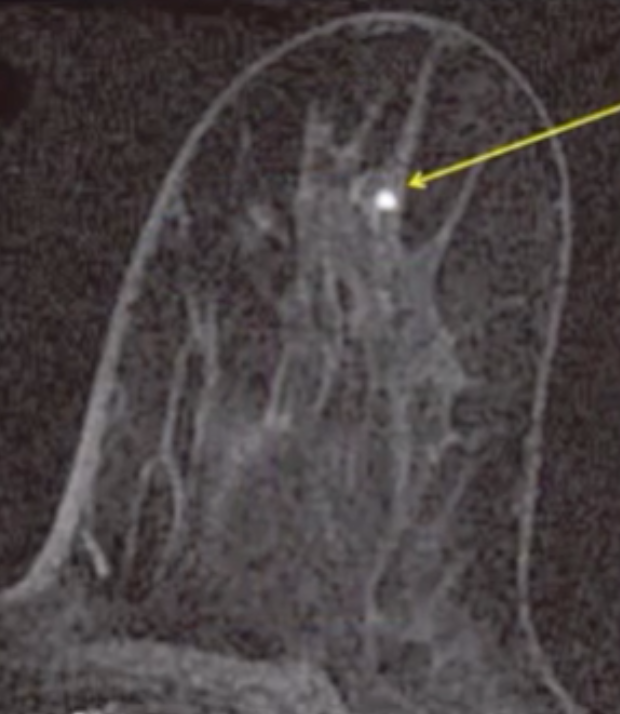

Foci

• Dot of enhancement <5 mm

• Too small to otherwise characterize

• Multiple enhancing foci is lumped in with the background enhancement, not a BR2 just background breast tissue basically